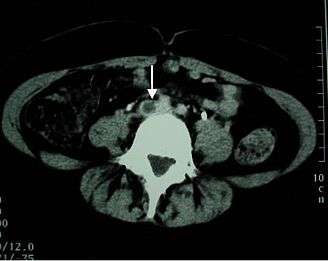

![]() The femoral vein (in the thigh), the iliac veins (in the pelvis), and the inferior vena cava (in the abdomen) are places of potential DVT extension. |

DVT often develops in the calf veins and "grows" in the direction of venous flow, towards the heart.[33] When DVT does not grow, it can be cleared naturally and dissolved into the blood (fibrinolysis).[34] Veins in the calf or thigh are most commonly affected,[35] including the femoral vein, the popliteal vein, and the iliofemoral vein (as with May–Thurner syndrome). Extensive lower-extremity DVT can reach into the iliac vein of the pelvis or the inferior vena cava.[36] Occasionally the veins of the arm are affected, as after central venous catheter placement and with the rare Paget–Schrötter disease.[26]